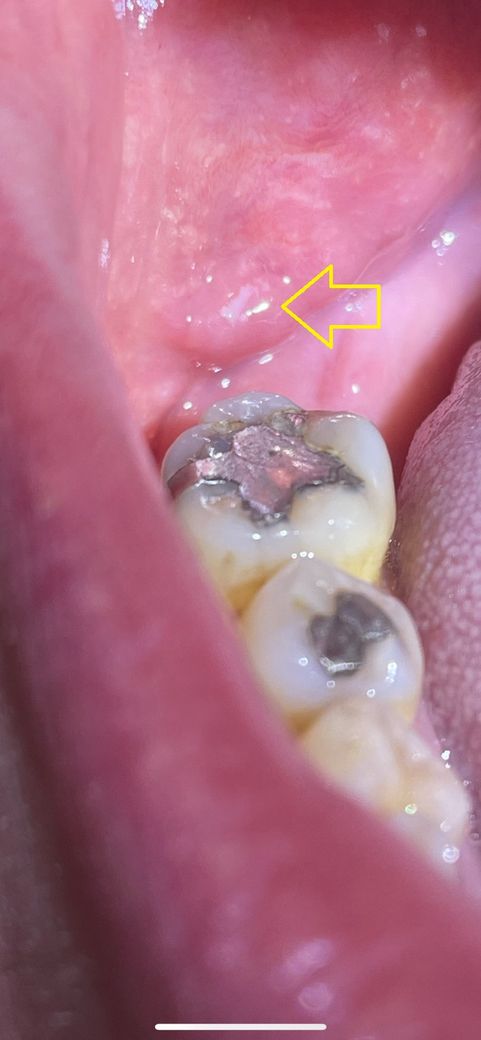

화살표로 표기한곳 부풀어 있는데 괜찮은건가여?

하얀색은 칫솔질 하다가 부딛혀서 치유 되고 있는거 같고

통증이 있거나 하지 않습니다

단순히 칫솔이나 외부 자극 혹은 음식물에 의해 나타난 상처로 보여지며 정상적인 회복 과정으로 보입니다. 하지만 사진 상으로는 회복과정인지 구내염인지 그리고 연조직 병소인지 정확한 판단이 어렵기 때문에 2주 이상 회복되지 않고 계속해서 나타난다면 이때는 치과 방문 후 감별진단을 받아보셔야 합니다.

사진에 보이는 하얀색은 점막에 상처로 인해서 감염이 된 구내염을 보입니다.

대부분 시간이 지나면서 괜찮아 지지만 오라메디 등의 연고를 받으면 치유가 빨라 질수 있습니다.

크게 이상이 있는건아니고, 아마도 치아에 씹혓거나 어떤 자극에 의해서 생기는 상처 같은겁니다. 시간이 지나면 괜찮아 지실꺼에요.